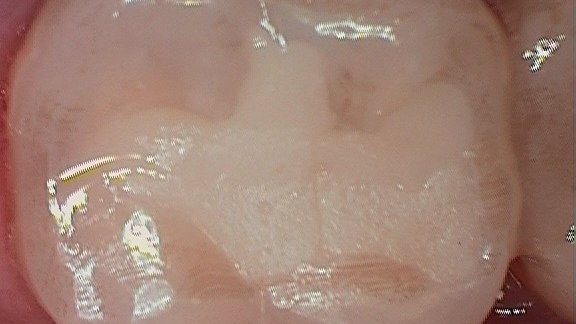

Figure 1 shows a large radiolucency on the mesial and a small radiolucency on the occlusal of tooth 31. Figure 2 shows an initial caries lesion on the distal pit and a leaking occlusal composite. Tooth 31 was sensitive to cold but normal to chewing, bite, and heat. Selective caries removal was used to prevent pulp exposure and preserve the marginal ridge.

Figure 3 shows the final restoration immediately after placement. Figure 4 shows the final restoration of an initial caries lesion on the buccal. The clinician anticipated maturation of the glass-hybrid in choosing a lighter shade of A2, which initially appeared much too light. A slightly darker shade may have been more appropriate.